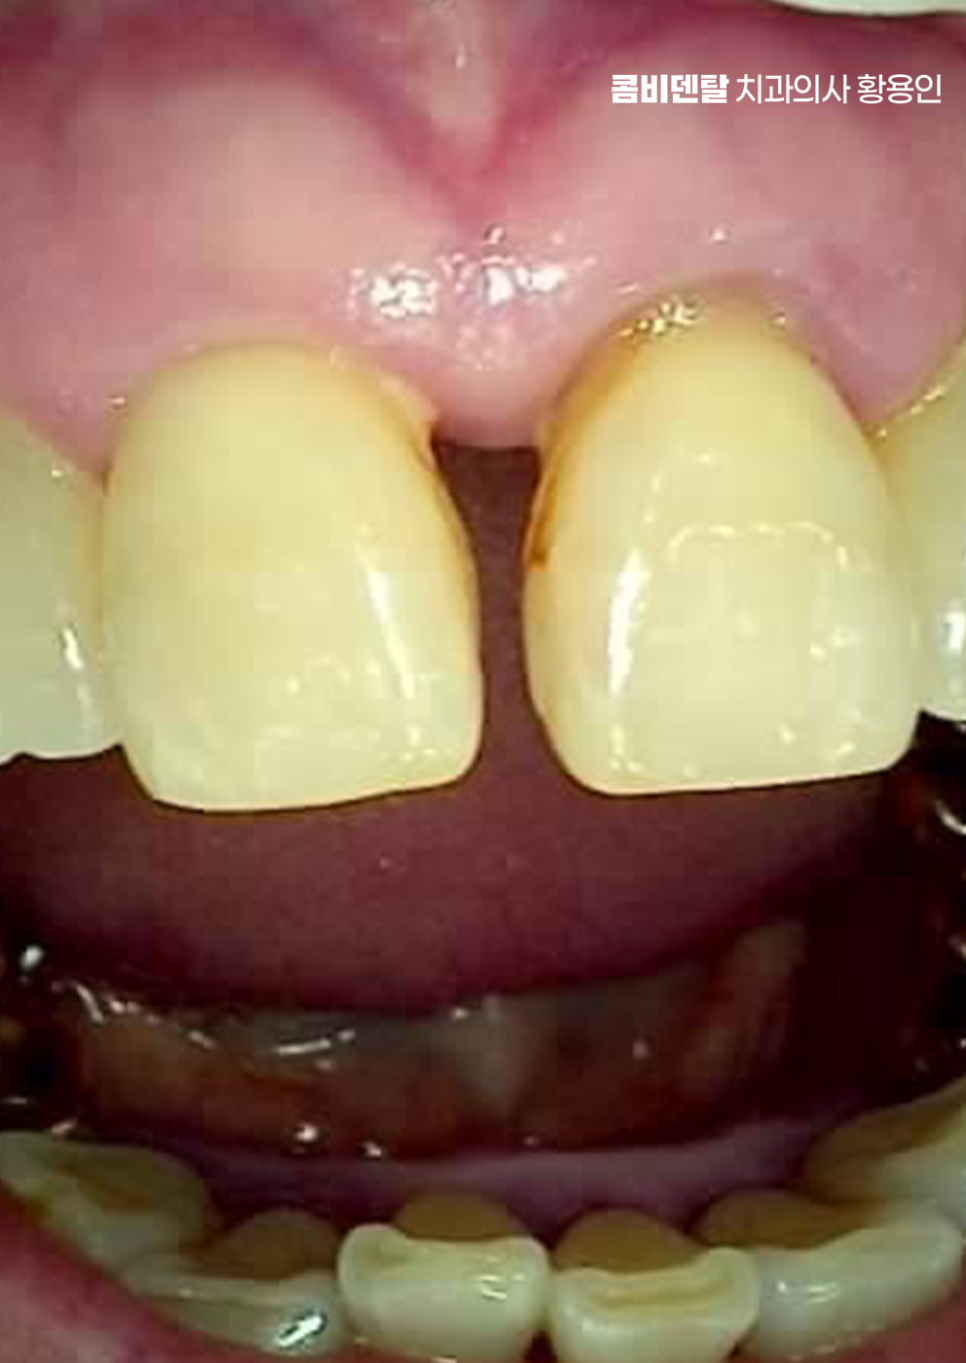

출처 아카이브 열기처음엔 그저 잇몸이 조금 붓는 정도였어요. 양치할 때 피가 나는 것도 자주 있는 일이니까 대수롭지 않게 넘겼어요, 치실을 쓰다가 피가 묻어 나오는 건 오히려 "잘 닦고 있구나" 하고 착각했어요. 그런데 어느 날부터인가 그 붓기가 자주 반복되기 시작했고, 입 안이 자꾸 텁텁하고, 입 냄새도 예전보다 쉽게 났어요, 양치를 아무리 열심히 해도 개운하지 않은 느낌이 계속됐어요. 그러면서 잇몸이 서서히 내려앉기 시작했고, 그 변화가 눈에 보이기 시작한 순간부터는 더 이상 가볍게 넘길 수 없었어요. 예전보다 치아 뿌리 쪽이 더 드러나 보이고, 잇몸선이 들쑥날쑥해지면서 거울을 볼 때마다 마음이 무거워졌어요. 크게 달라진 건 치아 사이가 눈에 띄게 벌어지기 시작했다는 거였어요.

이처럼 나이가 들수록 치아 사이 벌어짐이 잇몸이 약해지면서 더욱 심해지는 경우가 많은데 이러한 문제는 단순히 치아 배열만의 문제가 아니라 치아 수명과도 직결될 수 있는 큰 문제로도 볼 수 있는데요

또 하나 고려해야 할 부분은 치아 사이의 삼각형 공간, 즉 ‘블랙 트라이앵글’로 치주질환으로 인해 잇몸이 내려가면, 치아는 제자리에 있어도 삼각형 모양의 틈이 생기는데 이 틈은 보기에도 좋지 않을 뿐더러 음식물이 자꾸 끼는 원인이 되기도 해서 교정이나 치주치료만으로 한계가 있는 부분은 보철치료를 적절히 연계하여 치료하는 것도 경우에 따라서는 필요할 수 있어요.